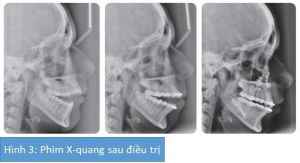

Khớp cắn sau cùng ở hình 2 và 3

Bệnh nhân nữ 17 tuổi hiện có sai khớp cắn hạng II tiểu loại 1 trên nền xương hạng II với tăng kích thước dọc và mất đối xứng hàm dưới, phức tạp hơn bởi khớp cắn hở phía trước (12mm) và chen chúc ở cả 2 cung răng.